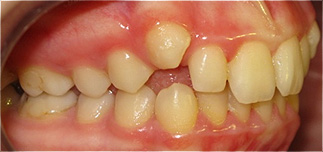

Dente canino não erupcionado e apinhamento dentário.

Criação de espaço para tração do dente canino, após 6 meses de tratamento.